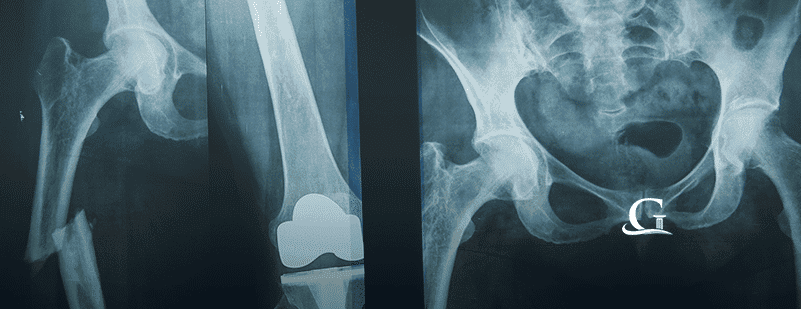

DePuy Knee Replacements Recalled October 18, 2017DePuy, a subsidiary of Johnson & Johnson, are the subjects of a massive knee replacement recall issued by the FDA on two of their artificial…

Which Hip And Knee Replacements Are Known To Fail? July 12, 2017Knee and hip replacements continue to increase in numbers. As baby boomers continue to age and require more medical care, hip and knee replacement options…